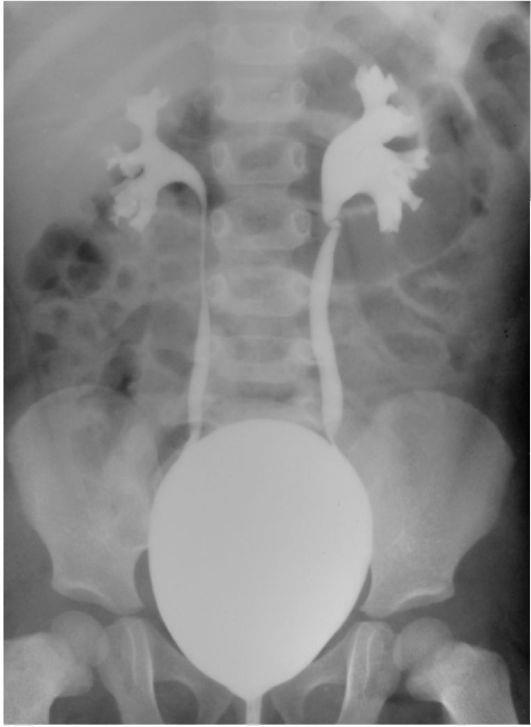

Медицинские изображения и примеры эксреторной цистографии